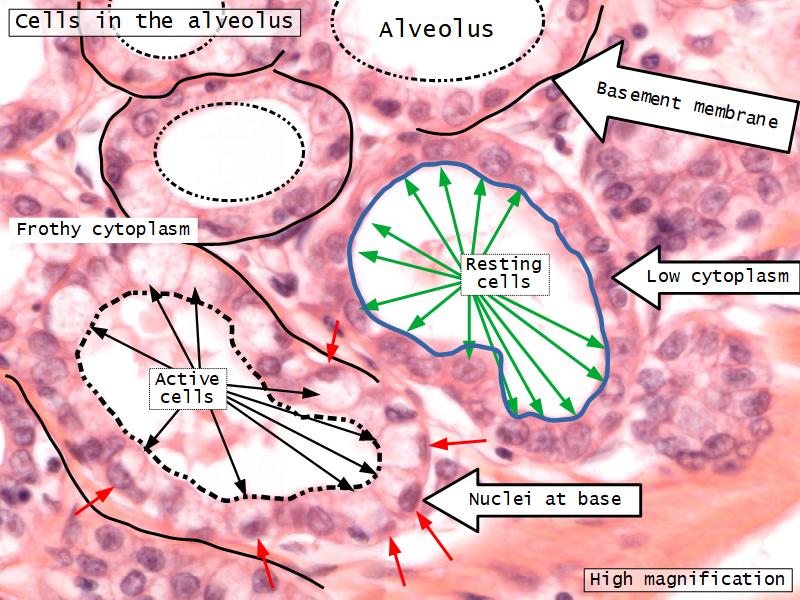

Mammary gland

Write short notes describing the structure of the mammary gland.

(5)

Mammary gland

- Compound tubuloalveolar gland

- 12 - 20 glands

- Each with own lactiferous duct

- Each with own lactiferous sinus

- Opens on skin at apex of nipple

Two stages

- Resting

- Active

Resting and active

Describe the resting mammary gland and compare with the active gland.

(8)

Resting gland

- Connective tissue dominate

- More adipose tissue

- Glandular tissue reduced

Active gland

- Terminal ducts expand

- Forms alveoli

- Connective tissue reduced

- Adipose tissue reduced

- Glandular tissue dominate

Active gland

- Much larger than resting phase

- Terminal ducts proliferate to form alveoli

- Alveoli

- Surrounded by incomplete myoepithelial cells

Alveolar cells

- Apocrine secretion

- Active state

- Resting state